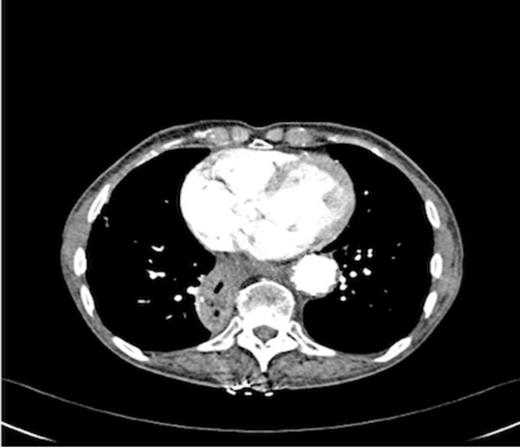

An endoscopy performed four years post-operatively demonstrated two atypical acute gastric ulcers in the distal stomach (figure 1), which were treated with a heat probe (figure 2). Two days later she presented as an emergency in hypovolaemic shock following a large volume haematemesis (haemoglobin of 40g/l). An urgent upper gastrointestinal endoscopy revealed a visible vessel at 35 cm forming part of an expansive mass within the gastric conduit. EUS demonstrated a heterogeneous mass indenting the gastric conduit, containing a strong Doppler signal (figure 3). An urgent computerised tomography (CT) angiogram revealed a Type-A thoracic aortic aneurysm with an enteric fistula (figure 4). The saccular aneurysm of the thoracic aorta was embedded in the gastric conduit. A 28x16cm Valiant® (Medtronic Ltd, Minneapolis, USA) stent was placed in the descending thoracic aorta with good occlusion of the aneurysm. The patient made an excellent recovery and was discharged on the seventh day post stenting.

Post operatively the patient developed a low grade stent infection requiring a prolonged course of antibiotics as an outpatient. Two years after insertion of the stent she remains well with no further gastrointestinal bleeding and follow up endoscopy has shown intact mucosa at the site of fistula. Computerised tomography scanning has demonstrated involution of the aneurysm sac and no endo-leak (figure 5).